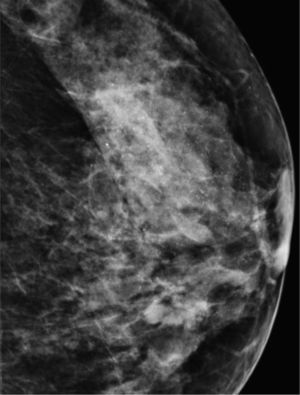

Carcinoma ductal in situ (fig. 10). Es el carcinoma que con mayor porcentaje se presenta en forma de microcalcificaciones. Representa el 15-20% de los cánceres de mama3. Se detecta por mamografía más que por exploración clínica. Las microcalcificaciones corresponden a la necrosis central de la neoplasia, ocupan el conducto y son producidas por procesos proliferantes en los conductos terminales7. Suelen ser amorfas, espiculadas y con ramificaciones irregulares.